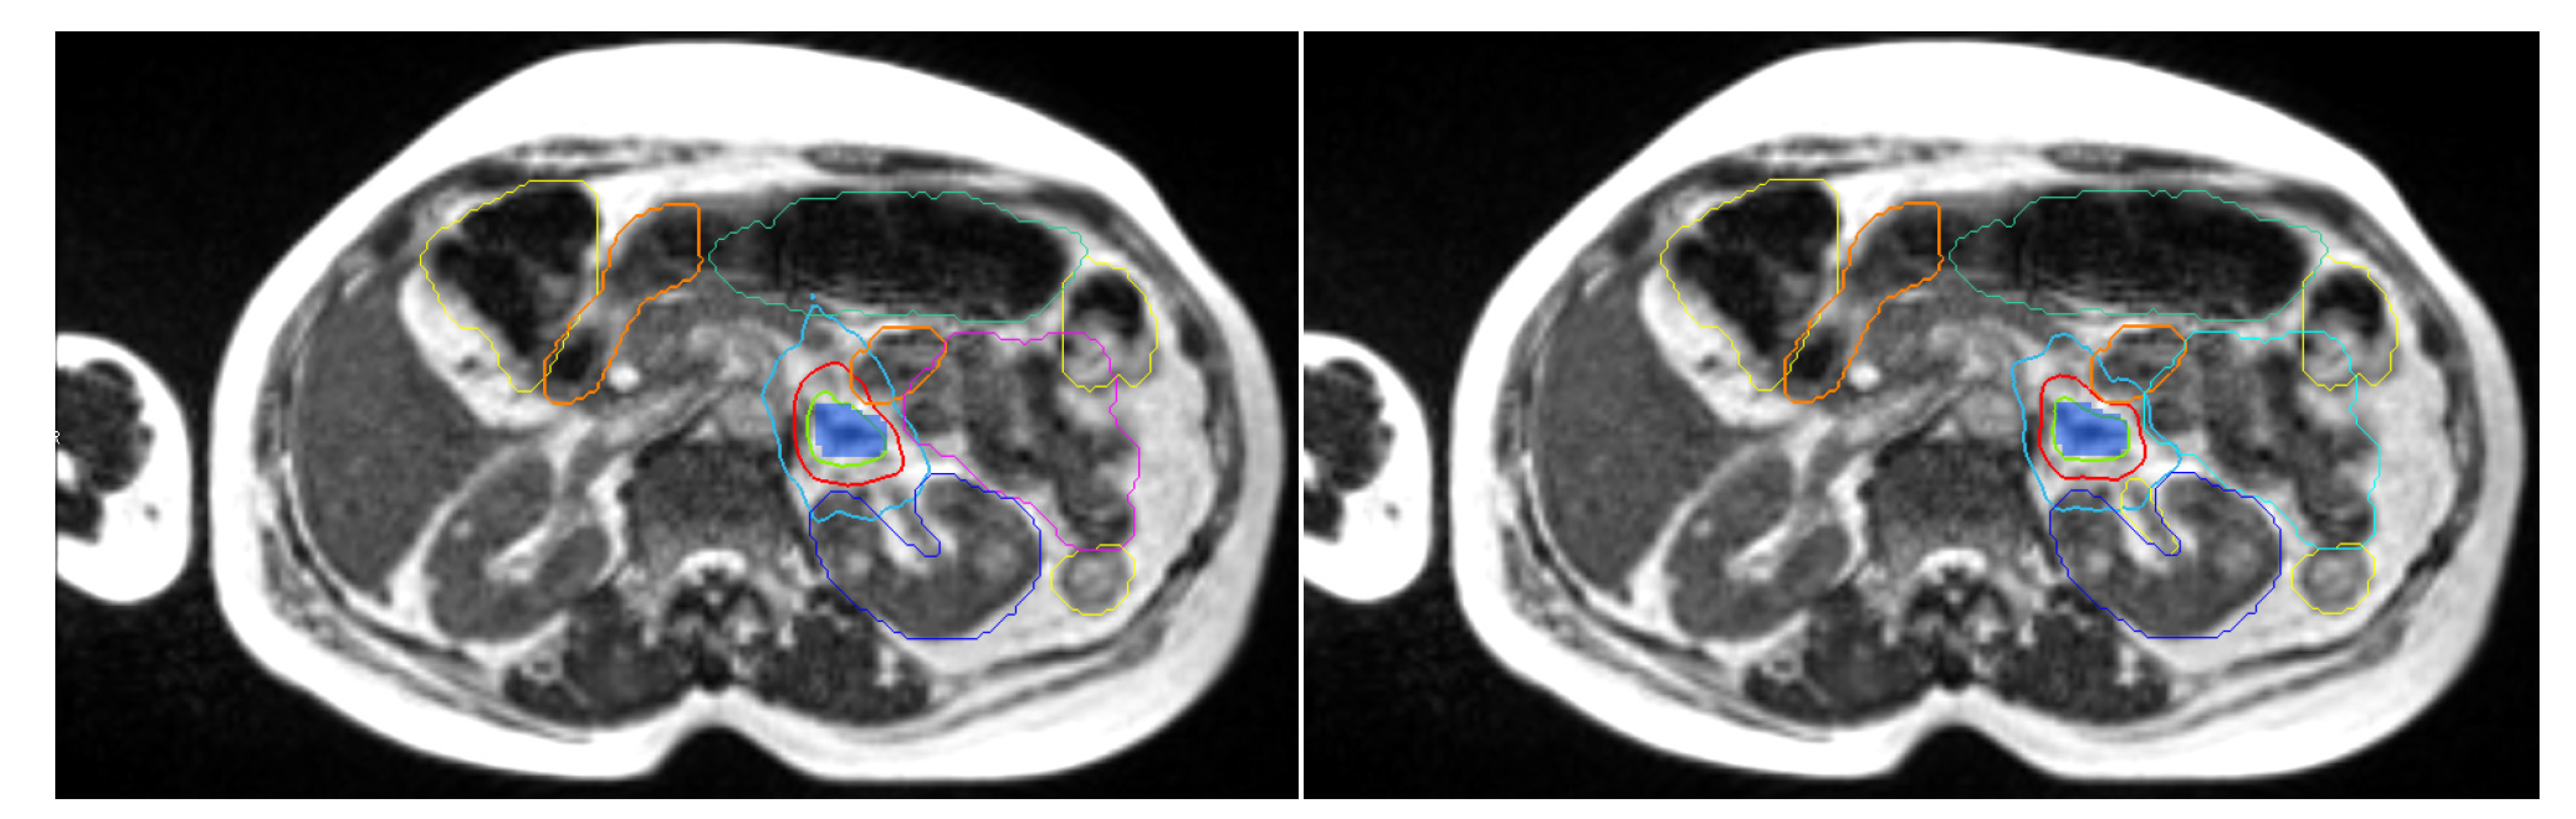

2.5. Daily Adaptive Treatment Workflow

3.3. Dosimetric Benefits of Adaptive MRgRT